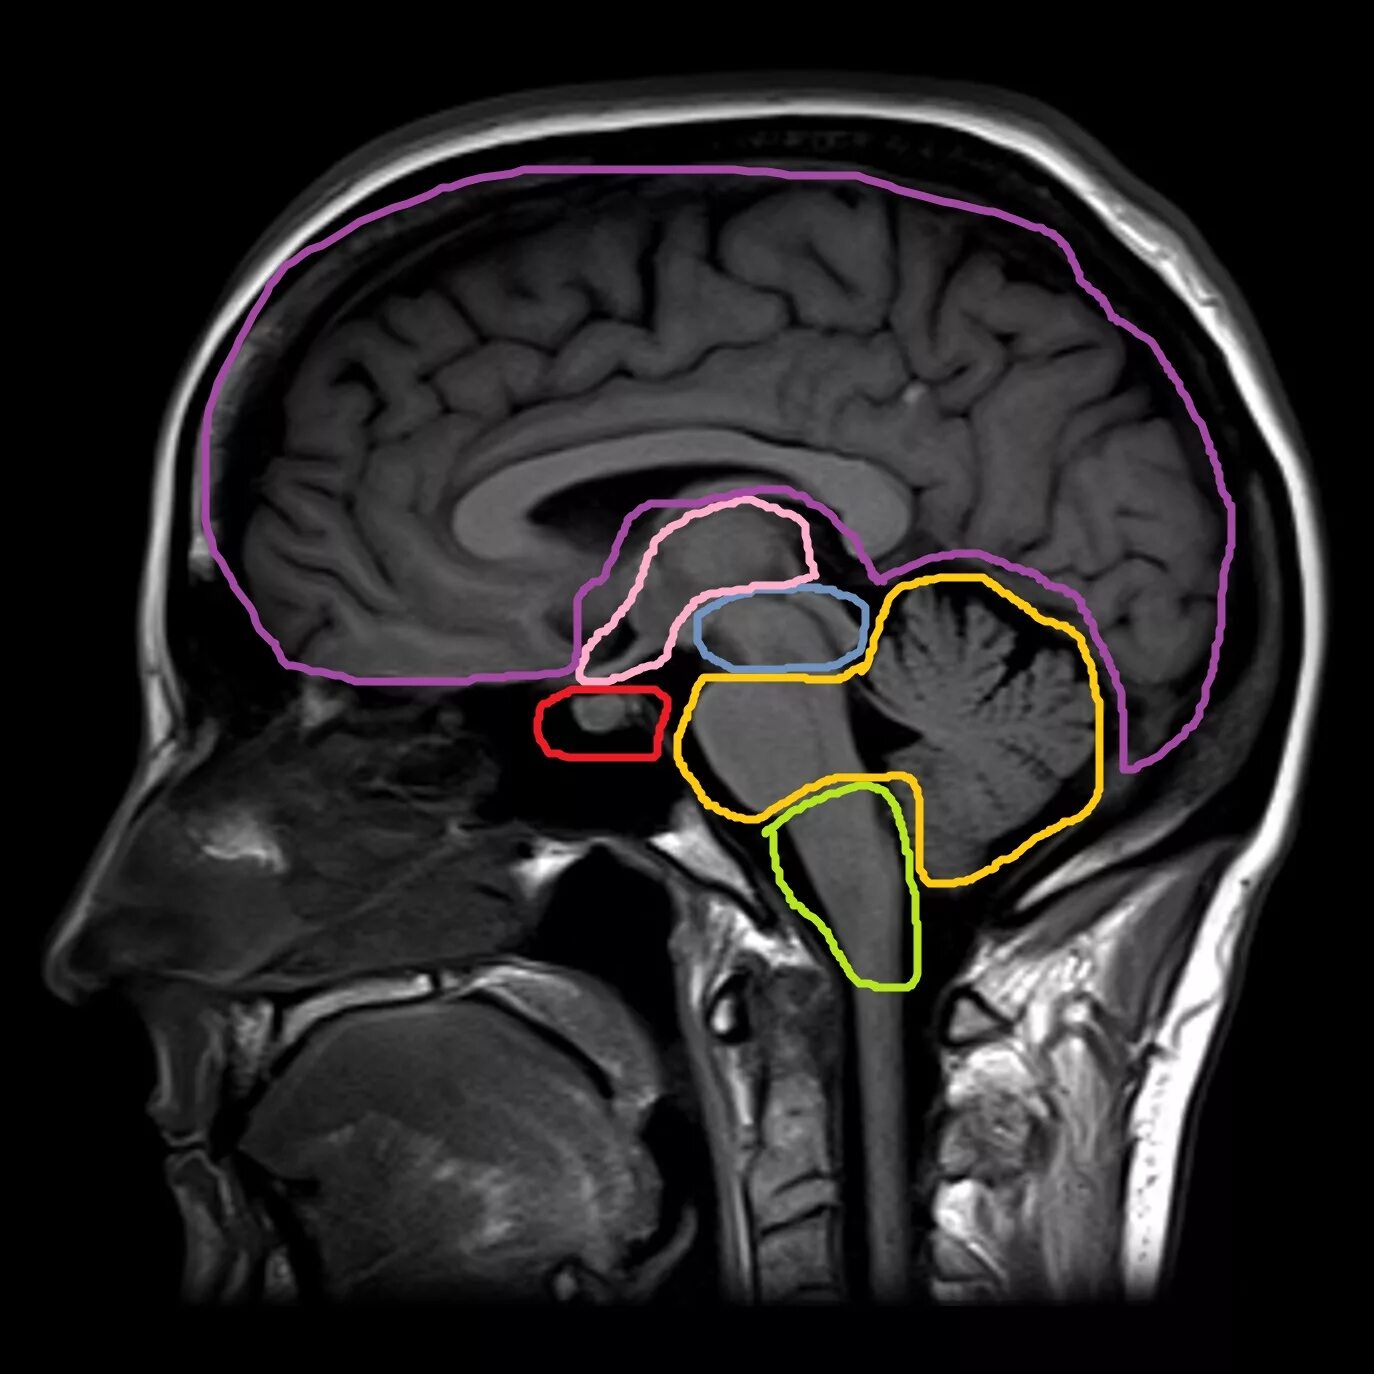

Субарахноидальное пространство зрительных нервов